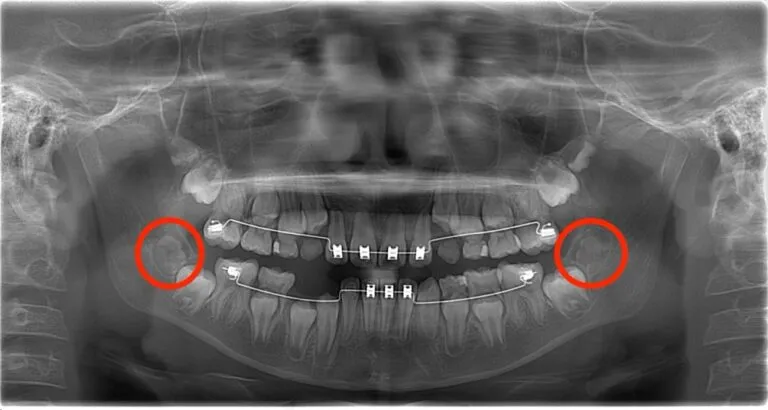

症例:歯胚抜歯のBefore / After

Before:矯正治療中の歯胚の位置異常

- 手前の歯を押す

- 歯列を乱す

- 矯正治療後の“後戻り”を起こす

といった問題が予測される状態です。

このような歯胚は、成長するにつれ抜歯が難しくなるため、早期の判断が重要となります。